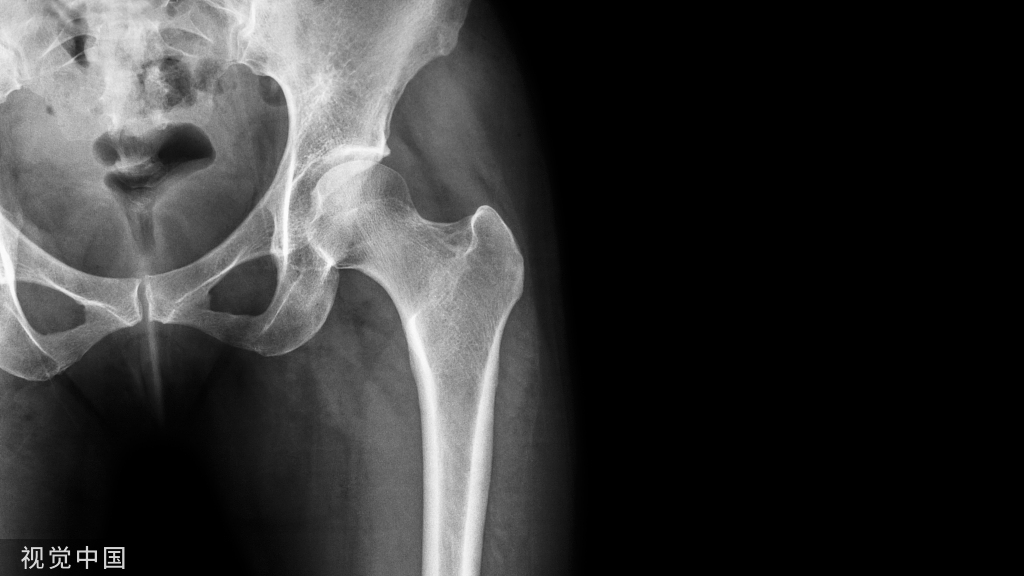

股骨粗隆间骨折,是老年人常见的骨折。随着社会的老龄化,人均寿命的延长,骨质疏松人数的增加,老年人发生股骨粗隆间骨折的概率呈上升趋势。

股骨粗隆间骨折,是老年人常见的骨折。随着社会的老龄化,人均寿命的延长,骨质疏松人数的增加,老年人发生股骨粗隆间骨折的概率呈上升趋势。粗隆间骨折的治疗面临巨大挑战,存在的最主要问题是出血量大、死亡率高、内固定失效、畸形愈合。